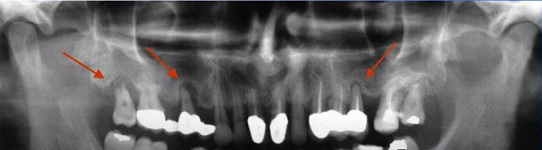

Onemocnění parodontu patří ke druhému nejčastějšímu onemocnění v dutině ústní, ihned po zubním kazu. Nejčastějším problémem je gingivitis- zánět dásní a také parodontitis - zánětlivé onemocnění postihující závěsný aparát zubů, přilehlou dáseň i kost. Mezi časné projevy gingivitidy patří krvácení dásní, které může v případě parodontitidy přejít ve tvorbu parodontálních chobotů, spojené se zápachem z úst, tvorbou hnisu, bolestmi a viklavostí zubů v důsledku ztráty kosti. Tomuto onemocnění se dá úspěšně předcházet pravidelnými kontrolami, sanací chrupu a péčí v rámci dentální hygieny.

Používá se i v implantologii, při stanovení diagnózy a léčby periimplantitidy (zánětu měkkých tkání a kosti v okolí implantátu).